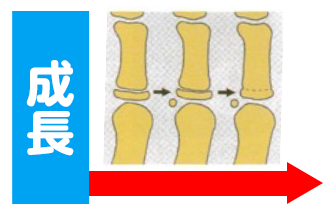

①呼吸は今しか改善できません

鼻腔は15歳まで成長します。この時期までに鼻で呼吸すると、鼻腔が刺激され成長します。

その結果、鼻腔の空気の通りが良くなり鼻閉が改善されます。

これが鼻腔のバルーン効果と言います。